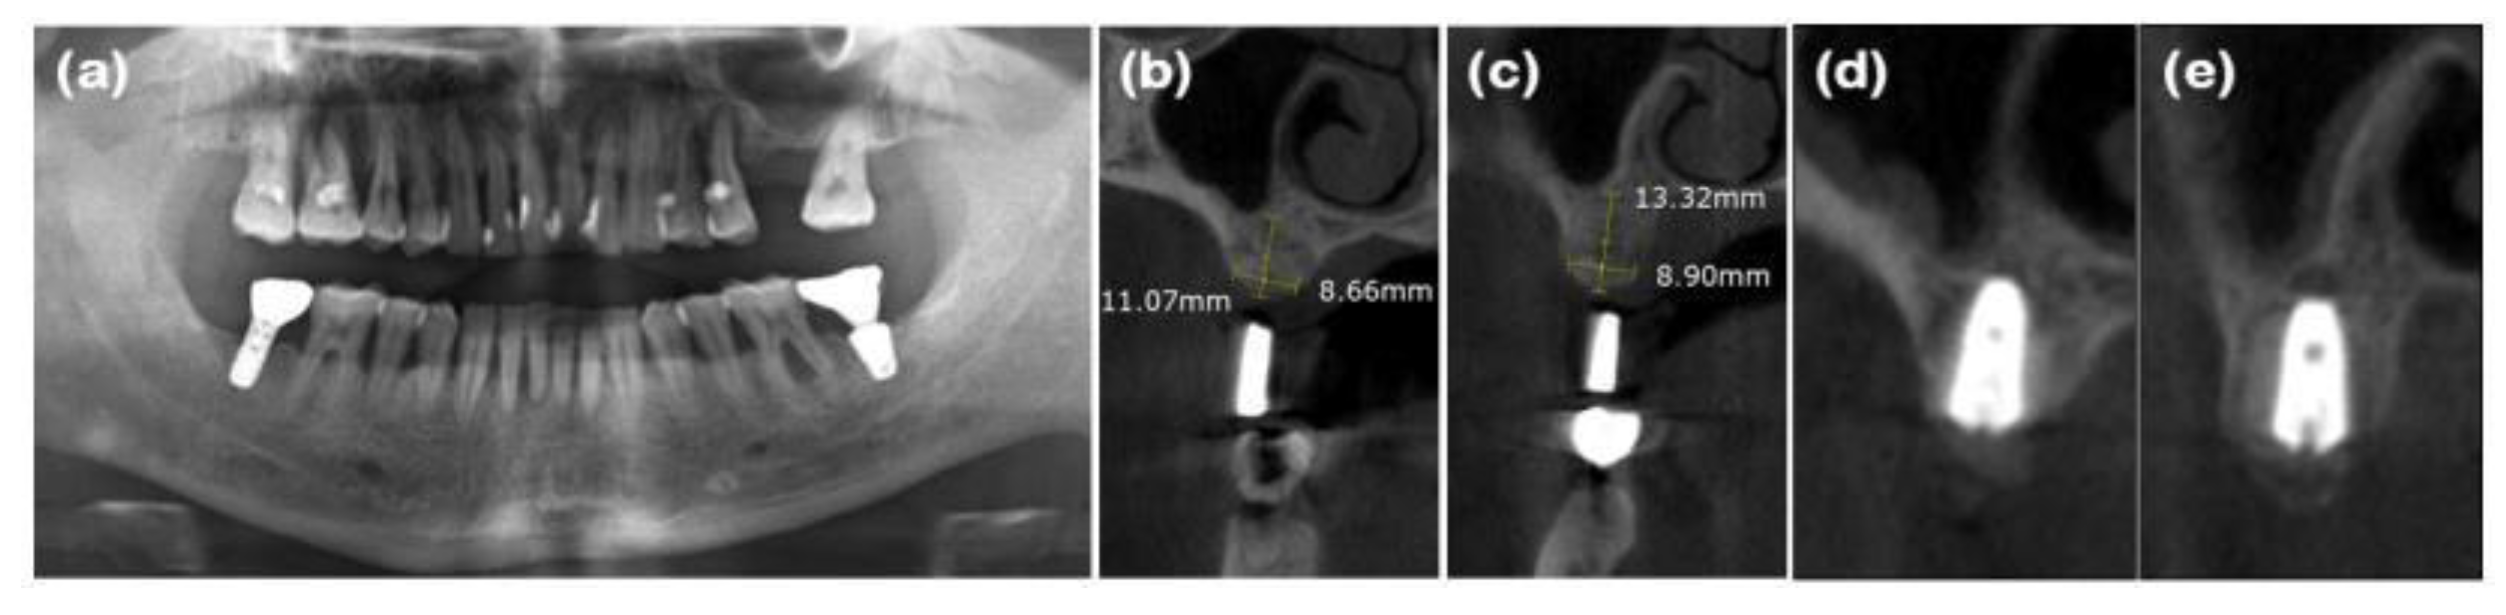

Figure 4. Radiographs of case 2. (a) Pre-operative panoramic view taken during the initial visit. (b and c) CBCT images displaying the augmented site after healing. Alveolar ridge width was measured at approximately 8.66 and 8.90mm on the maxillary right first and second molar areas, respectively, which is sufficient for the placement of a standard diameter implant. (d and e) Implants were placed in the maxillary right first and second molar areas, respectively.

First, full-mouth scaling was performed. After the extraction of #16 and #17, a full-thickness flap was elevated, revealing buccal and palatal bone loss at the #16 site (Figure 3a and 4a). Xenograft mixed with collagen (Bio-Oss collagen® (Deproteinized bovine bone mineral with collagen), Geistlich Parma AG, Wolhusen, Switzerland) was applied to the extraction sites of #16 and #17, and a resorbable collagen membrane (Bio-Gide compressed®, Geistlich Parma AG) was placed over the graft (Figure 3b). The incision was extended due to the posterior flap design, which increased flap elevation, and there was significant alveolar bone loss and soft tissue deficiency at the #16 extraction site. Even with secondary healing, it was anticipated that the newly regenerated soft tissue would be thin and insufficient. Therefore, along with ARP, a xenogenic collagen matrix (Mucograft®, Geistlich Parma AG) was applied. Hidden-X sutures [9] and simple interrupted tension-free sutures were placed using 4-0 Biotex (Purgo Biologics, Seongnam, Korea), and secondary healing was intended (Figure 3c). Upon suture removal 10 days later, secondary healing was confirmed, and the patient was monitored. Ten months later, a full-thickness flap was elevated for implant placement, and the augmented alveolar bone width of 8 mm was observed (Figure 3d, 4b, and 4c). The implant was placed in the ideal position (Superline Φ5.0×10 mm, Dentium), and GBR (Bio-Oss® and Bio-Gide compressed®, Geistlich Parma AG) was performed to compensate for the graft material lost during drilling (Figure 3e, Figure 4d, and 4e). Five months after the first implant surgery, the second implant surgery was performed, and the final prosthesis was placed 7 months after the first implant surgery (Figure 3f). Clinical examination revealed stable horizontally and vertically augmented alveolar bone and 6 mm of keratinized mucosa around the implant on the buccal side.

In this study, ARP was performed with flapped surgery in patients who required horizontal and vertical bone augmentation due to the absence of residual bone. A collagen matrix was used to compensate for ridge contraction and to increase the keratinized mucosa around the implants. In case 1, the buccal bone plate at site #23 had been resorbed, resulting in a narrow alveolar ridge width in the bucco-palatal direction, which was insufficient for implant placement. To augment the buccal bone, xenogenic bone graft material, two-types of resorbable collagen membranes, and a xenogenic collagen matrix were applied, sequentially. At the time of implant placement, a ridge width of approximately 5.93mm was observed bucco-palatally, and continuous, intact soft tissue regeneration, including preservation of the interdental papilla, was achieved. In case 2, the bone wall at extraction site #16 had resorbed, necessitating both bone and soft tissue augmentation for predictable implant placement. Periodontal flap surgery was also performed on the adjacent teeth, resulting in a wider incision. A xenogenic collagen matrix was applied to promote adequate soft tissue regeneration. At the time of implant placement, ridge widths of approximately 8.66 and 8.90mm were observed bucco-palatally at sites #16 and #17, respectively, along with a continuous soft tissue contour. In case 3, following the extraction of teeth #31, #32, #41, and #42, the buccal bone plate had been resorbed. After broad ridge augmentation, a xenogenic collagen matrix was applied to aid in soft tissue regeneration and preservation of the interdental papilla. At the time of implant placement, ridge widths of approximately 4.92 and 4.33mm were observed bucco-palatally at sites #32 and #42, respectively, along with continuous soft tissue contour. Upon completion of the implant prosthetics, a natural appearance of the interdental papilla was observed continuously. In case 4, horizontal and vertical alveolar bone defects were observed in explanted sites #46i and #47i, along with a shallow buccal vestibule and insufficient keratinized mucosa. A xenogenic collagen matrix was applied to the buccal and crestal side to ensure sufficient alveolar bone augmentation and keratinized mucosa for implant placement, and the modified Edlan–Mejchar technique was used to deepen the buccal vestibule. At the time of implant placement, ridge widths of approximately 7.90 and 5.58mm were observed bucco-palatally at sites #45 and #47, respectively, while maintaining the natural soft tissue appearance and deepened vestibule. In respect of the anterior teeth in case 1 and case 3, the PES/WES values ​​were measured as 7~8 points, confirming that although the periodontal defects were severe, good esthetic results could be obtained. In the CBCT cross-sectional view and clinical examination of all cases, the alveolar bone width was appropriate for implant placement of narrow diameter or more in the anterior region and regular diameter or more in the posterior region. In addition, the width of the buccal keratinized mucosa was confirmed to be consistently well-maintained at 2 mm or more in all cases. Although there are many opposing views, it is important to secure the presence of keratinized mucosa with more than a 2mm width around the implant for the health and maintenance of the implant [19].